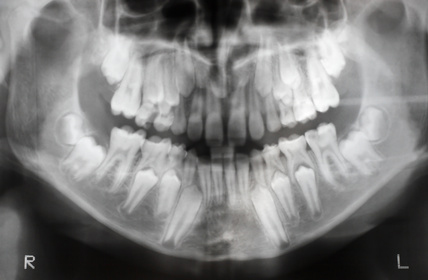

L’extraction d’une dent est toujours précédée d’un questionnaire (recherche de risques hémorragiques) et d’une radiographie.

Cet examen radiologique permettra de déterminer s’il faut procéder à une extraction simple ou à une extraction chirurgicale.